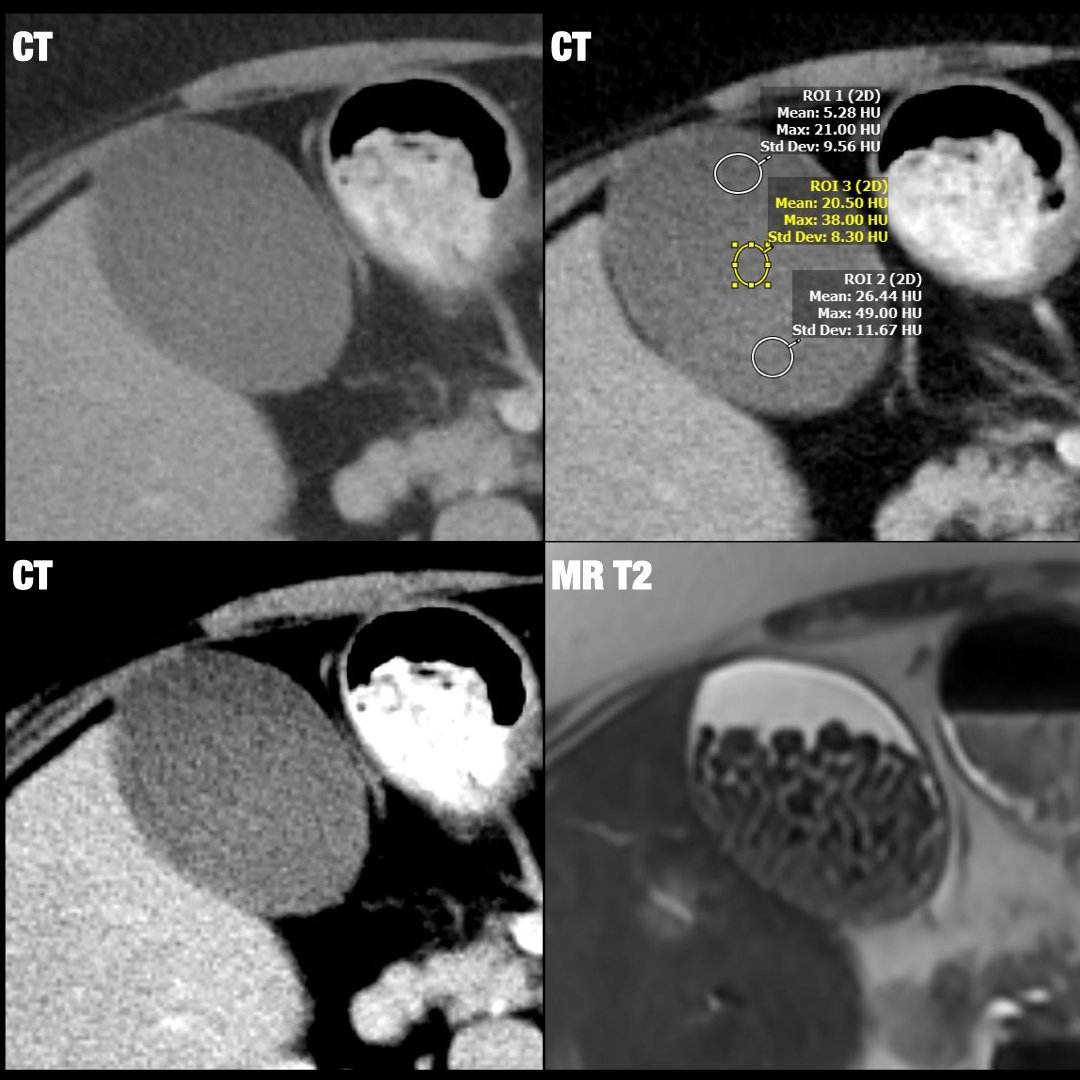

66 y/o male with ESLD admitted for hypoxia. Undergoing OLT evaluation

What is the diagnosis?

1. PFO

2. ASD

3. Pulmonary AVM

4. Anomalous pulmonary vein